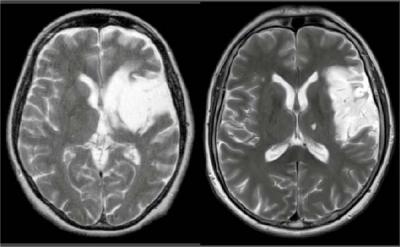

MRI was used to assess the exact brain areas affected in each patient. In both images, lesions can be seen in the left brain hemisphere (here on the right-hand side of each brain image).